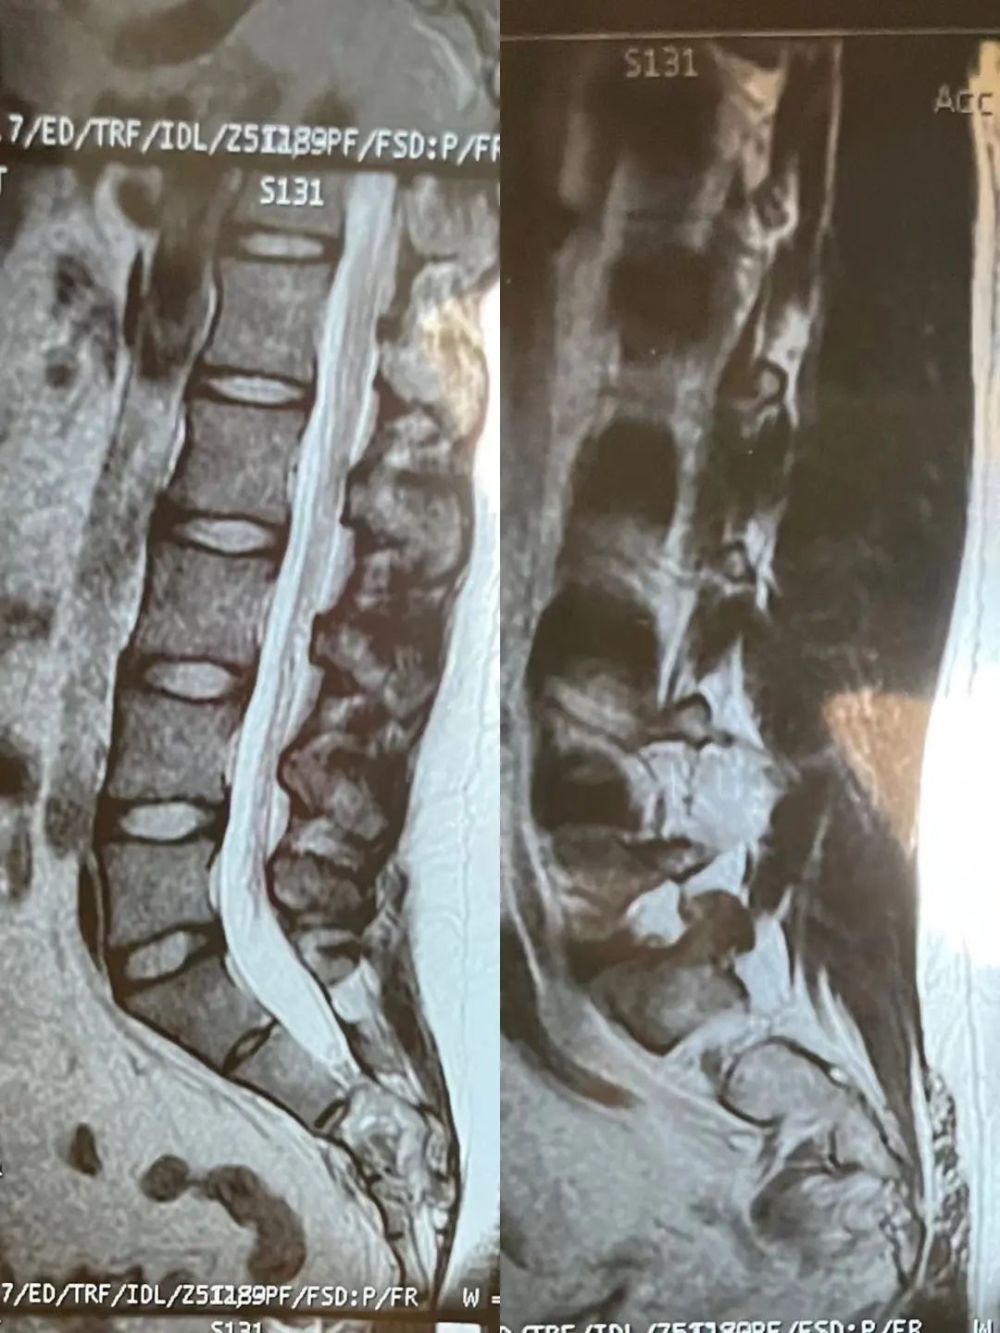

在绝望和痛苦中,我度过了漫长的住院期。好在全家人苦苦等待的病理“审判”,是良性的神经鞘瘤,而非斩不断的脊索瘤。总算是一个好消息。

最终病理诊断丨作者供图

骶骨肿瘤,顾名思义就是长在骶骨上的肿瘤,可分为良性肿瘤和恶性肿瘤。良性肿瘤如骨母细胞瘤、神经鞘瘤等,这些肿瘤会呈现扩张性生长。而恶性肿瘤最常见的是脊索瘤,会造成骶骨周围的骨质破坏,瘤体逐渐增大后会压迫神经,进而出现腿痛、大小便失禁等神经症状。

作者最终病理结果为神经鞘瘤。神经鞘瘤又称雪旺细胞瘤,是一种孤立性、有包膜、生长缓慢、由神经鞘细胞组成的良性肿瘤,它可发生于周围神经,椎管内也较常见。

神经鞘瘤在良性神经源性肿瘤中发病率最高,约占全部软组织肿瘤的5%。所有年龄均可发病,高峰发病期在20~50岁,发病率无性别倾向。

根据病史、体格检查,结合影像学检查,多数神经鞘瘤可以在术前基本诊断,但也有少数因部位较深、侵袭性生长等特点导致术前鉴别相对困难,影像学上同骶骨恶性肿瘤非常相近。神经鞘瘤的治疗主要采取手术切除的方式,神经轴突常形成肿瘤的包膜,可行包膜内肿瘤摘除。在肿瘤两端可见神经干,因肿瘤属良性,尽量不切断神经干。

神经鞘瘤最终诊断依赖于病理检查,其手术切除后很少复发,恶性变者罕见。手术治疗以单纯切除为宜,如无明显临床症状,可以随诊观察。较大并且生长在神经根附近的复杂病例术后亦会出现肢体疼痛、麻木、大小便功能障碍等并发症。